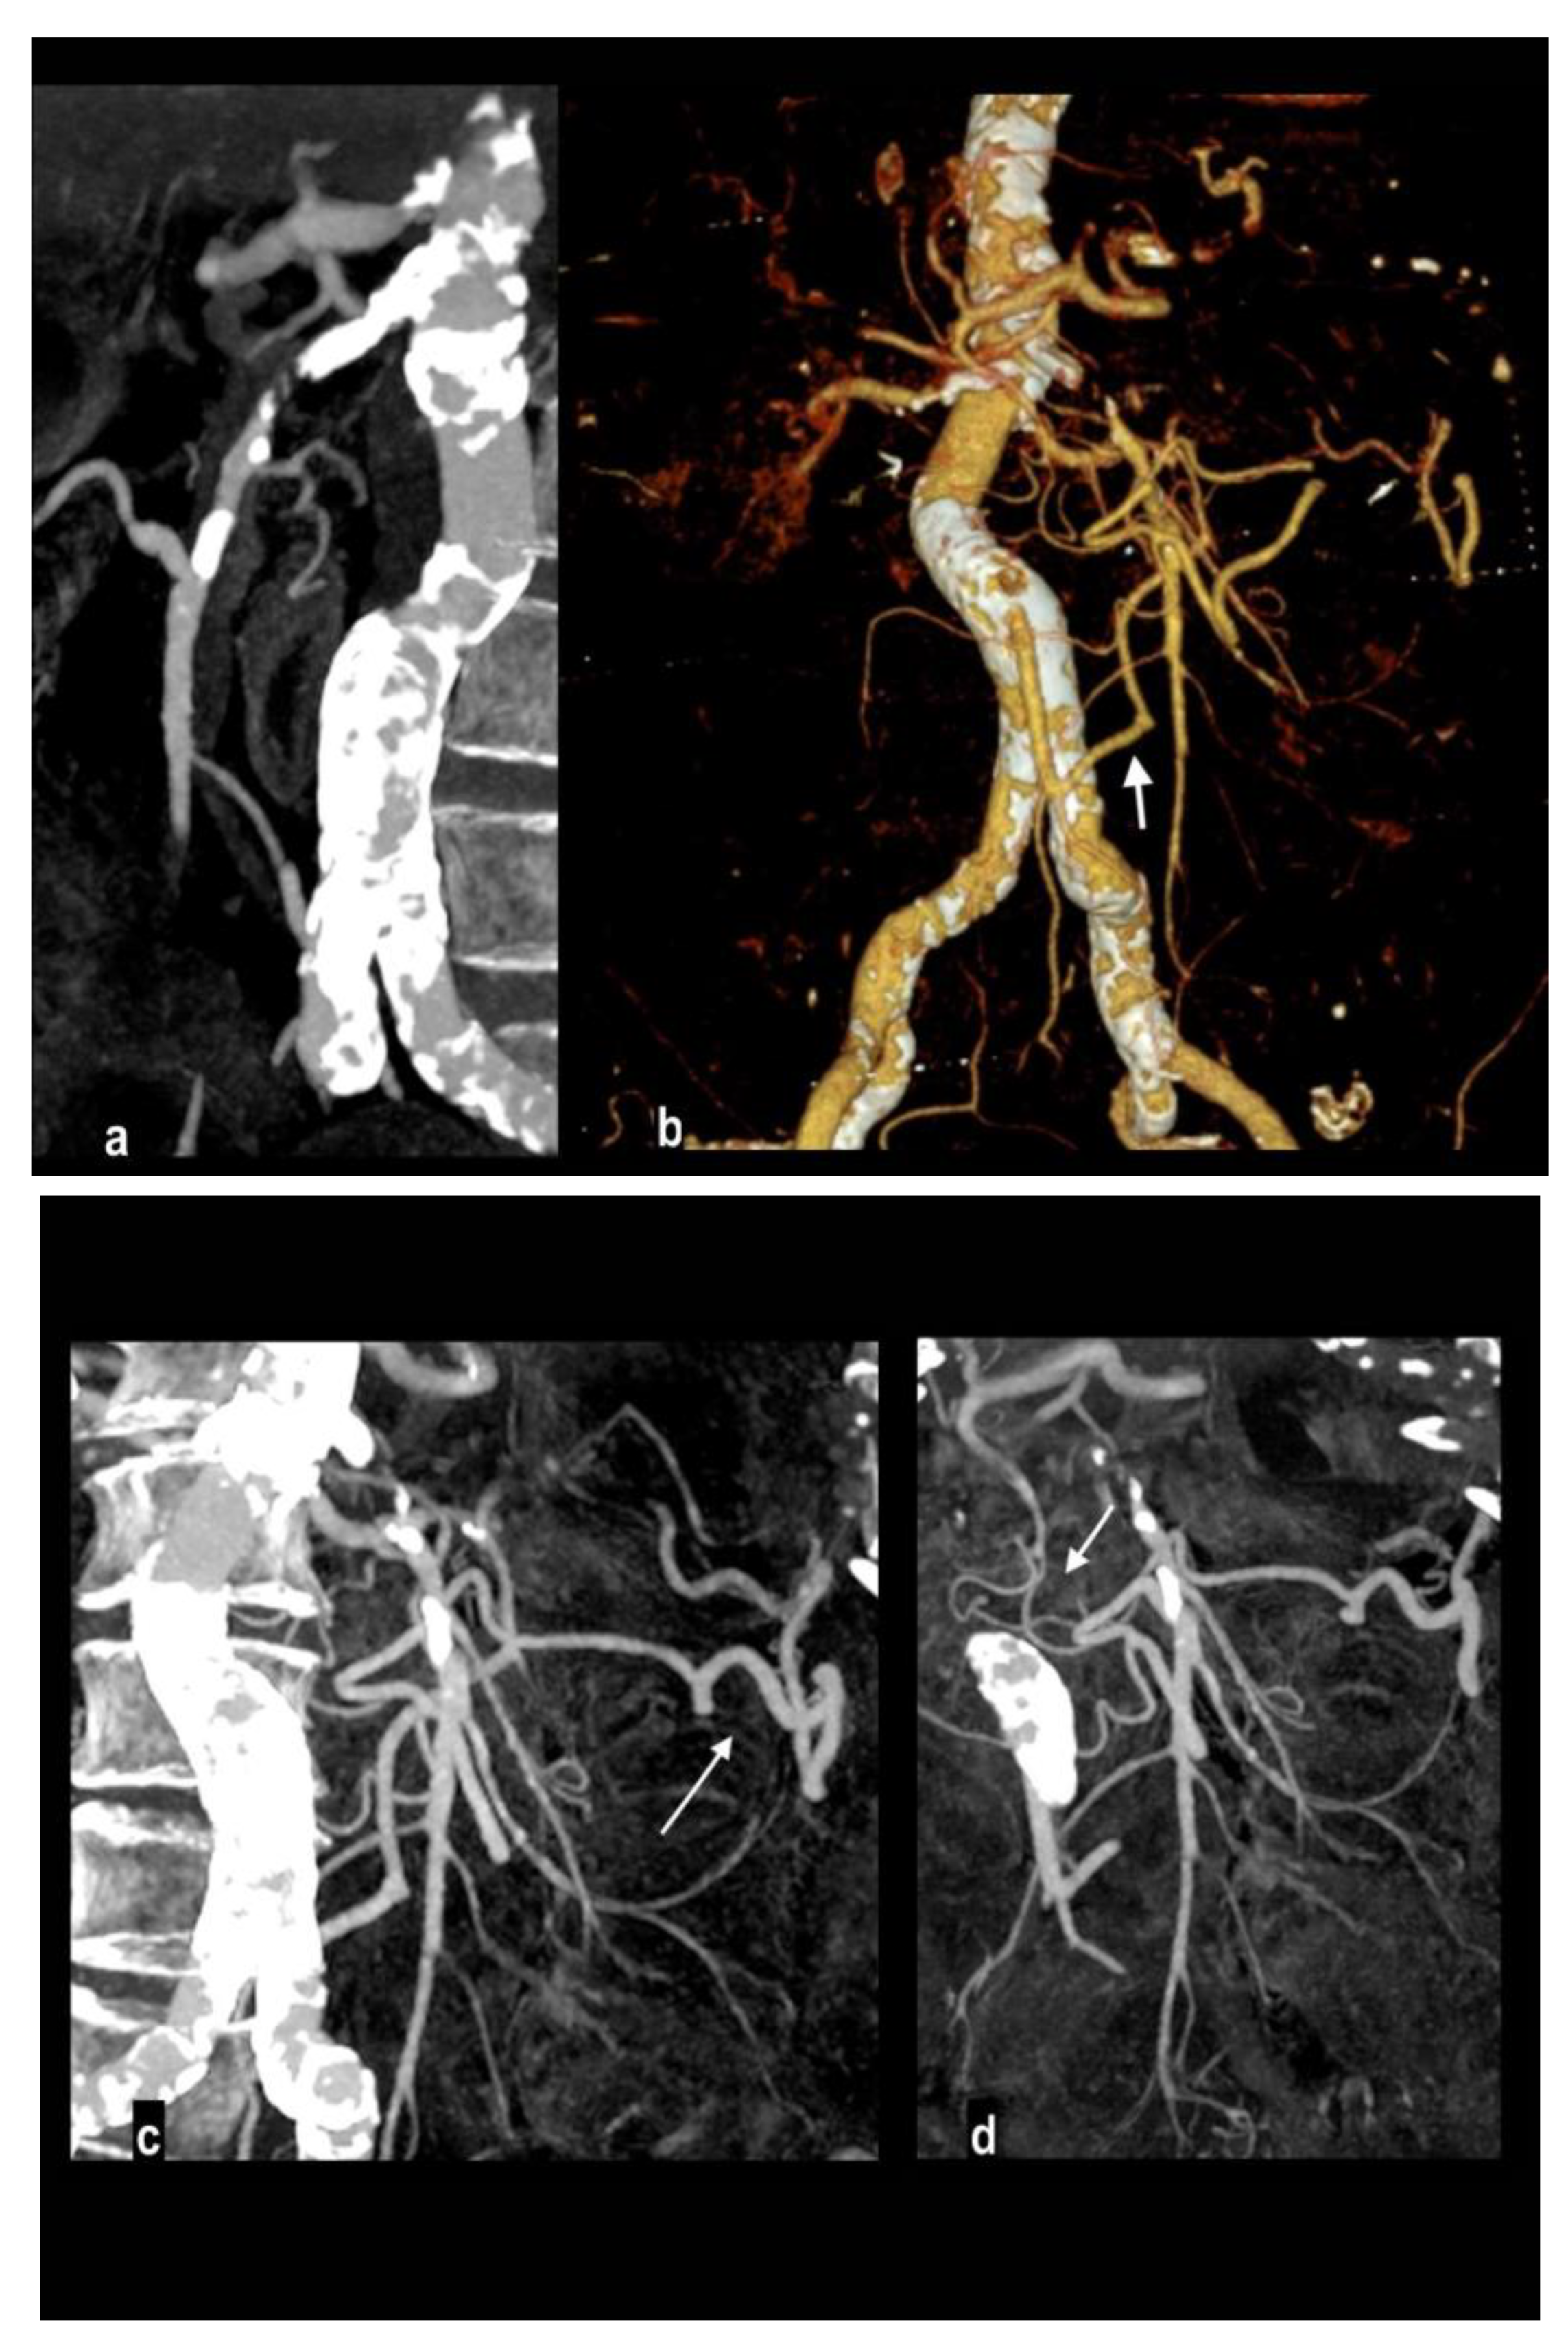

Figure 1. Abdominal pain in a 91-year-old woman with diffuse calcified vascular atheromasia. MIP arterial reconstruction (Figure 1a) showed calcified occlusion of proximal SMA and critical ostial occlusion of the celiac trunk. VR reconstruction (Figure 1b) well depicted an ectasis mesenteric inferior artery and a dilated Riolan artery (arrow), that allowed collateralization of the middle SMA and its branches. MIP reconstructions showed a large caliber of splenic flexure arteries (Figure 1c, arrow) and pancreatico-duodenal arteries (Figure 1d, arrow). However, a watershed territory (ileocaecal junction) didn’t receive appropriate hematic flow and caecum necrosis developed, with hypoenhancing wall thickness and parietal pneumatosis (Figure 1e, coronal MPR; Figure 1f, coronal MIP).